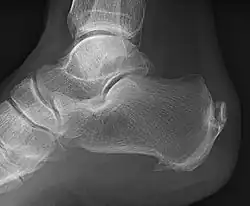

An enthesophyte, consisting of calcification deposits within the Achilles tendon at its calcaneal insertion. The Achilles tendon is wider than normal, further suggesting inflammation.